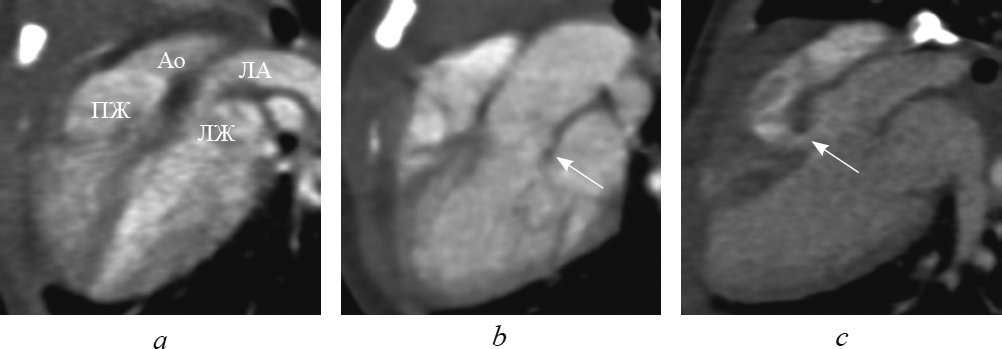

В данной статье приведены результаты анализа данных рентгеновской компьютерной томографии с внутривенным болюсным введением контрастного вещества детей с транспозицией и корригированной транспозицией магистральных артерий путем последовательного построения многоплоскостных реформаций, ориентированных на оси сердца. Из 148 детей со сложными врожденными пороками сердца и магистральных артерий транспозиция магистральных сосудов встречалась у 13 пациентов (в возрасте от 1 до 144 дней жизни; 9 — мужского пола, 4 — женского пола), корригированная транспозиция магистральных сосудов — у 4 пациентов (в возрасте от 6 мес. до 15 лет 6 мес.; 2 — мужского пола, 2 — женского пола). В статье подробно описаны анатомические характеристики, на основе которых определяется морфология каждой камеры сердца, и реформации, в которых они оцениваются. В статье приводится сравнительная характеристика структур сердца и магистральных артерий при транспозиции и корригированной транспозиции магистральных артерий в каждой отдельно взятой реформации, ориентированной на оси сердца. По результатам анализа последовательно построенных реформаций, ориентированных на оси сердца, указаны и проиллюстрированы характерные анатомические признаки транспозиции и корригированной транспозиции магистральных сосудов. Установлено, что из перечня предлагаемых реформаций, ориентированных на оси сердца, характерные анатомические признаки транспозиций достоверно определяются в следующих реформациях: по длинной оси приносящего тракта правого желудочка; левых камер сердца; приточных отделов желудочков; по короткой оси на уровне магистральных сосудов. Многоплоскостные реформации, ориентированные на оси сердца, на основе данных КТ-ангиокардиографии позволяют дать полную и точную анатомическую оценку сердца и магистральных сосудов, что важно при планировании оперативного вмешательства при врожденных пороках сердца.